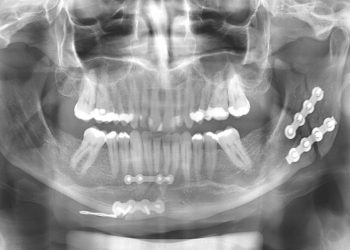

Ver mais...Esportes, quedas, acidentes automobilísticos, agressões e acidentes de trabalho são os principais fatores que ocasionam traumas faciais Traumatismos e doenças...